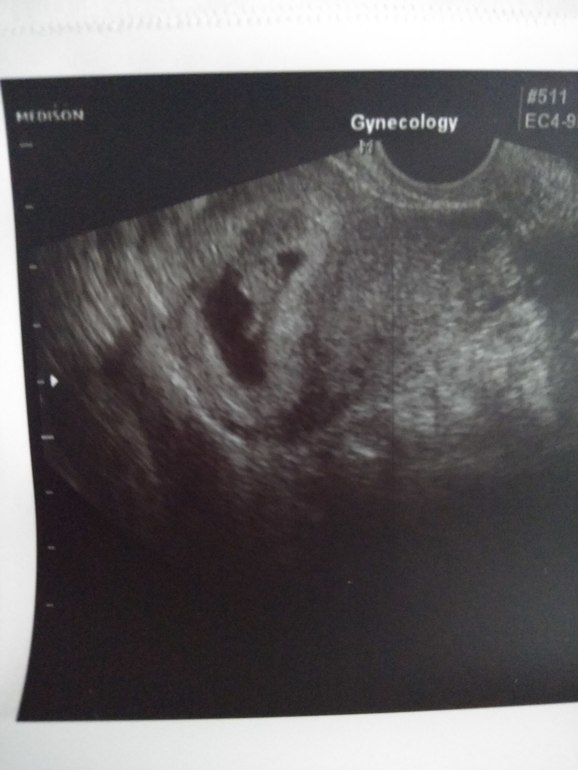

Сердечко у нашей креветочки бьётся, всё хорошо😊начинаем отменять дивигель, остальное всё без изменений)

Сегодня нам ровно 6 неделек. Кажется теперь я начала верить, что я беременна🤰😅сходила на УЗИ, крошке почти 4 недели, пя 13мм, эмбриончика не увидели, но нашли сердечко!!! Даже я сама увидела на мониторе как оно бьётся) дай нам боже спокойно выходить бе...